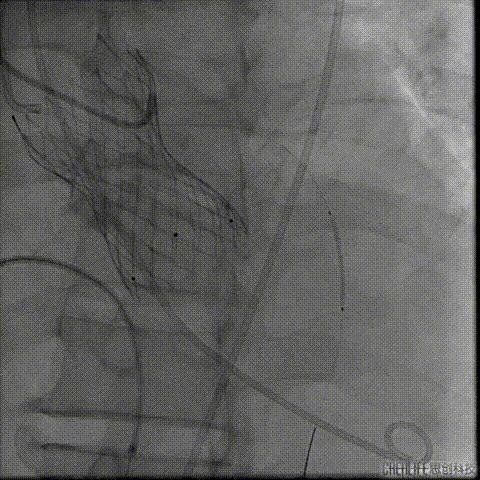

置入Venus-A32号瓣膜并释放

复查造影

撤出冠脉保护

再次复查造影

经瓣架网眼挂上指引管

反复确认指引管经瓣架网眼

指引管经瓣架网眼

经网眼置入导丝

置入4.0mm*23mm微创冠脉支架

定位并释放支架

退出球囊扩张突入瓣架部位

复查冠脉造影

多体位复查冠脉造影